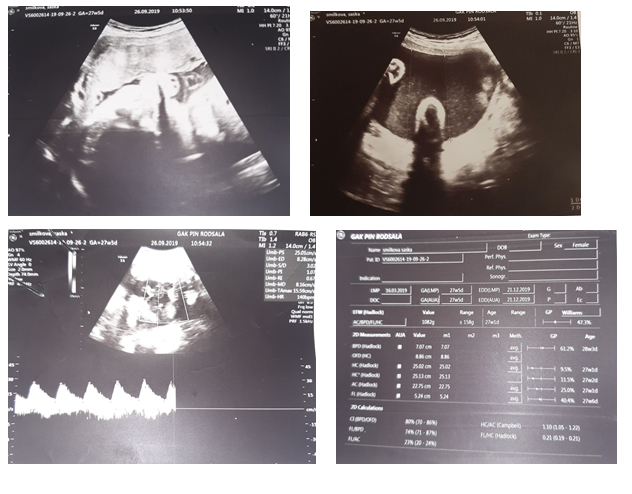

The next two controls were on a weekly basis until the 27th gestational week, when, due to malignant hypertension, she was initially admitted to the Department of Pathological Pregnancy, and then transferred to the Department of Peripartum Intensive Care. During the hospitalization, therapy for fetal lung maturation, antihypertensive and neuroprotective therapy was prescribed. A series of council examinations were performed by a nephrologist, cardiologist (correct findings), pulmonologist and otorhinolaryngologist. It was communicated with the patient with a sign language professional.

During hospitalization, high values of the angiogenic factors sFLT/PLGF up to 793.05, proteinuria 0.79g/L and malignant hypertension regulated by double antihypertensive therapy were determined. NST was reactive. The ultrasound finding was normal, the fetus had a normal fetoplacental flow.

After detailed anesthetic preparation, the patient was delivered by elective caesarean section at 28.5 weeks of gestation and a live female fetus was obtained with RTM=920g/35cm and AS=6/7/7. The intervention went smoothly. Postoperatively, the hypertension was regulated, the wound healed per primam, and she was discharged from the clinic on the third postoperative day. After 82 days of stay in the Department of Intensive Care and Therapy, the newborn was discharged in a stable condition and current weight of 1920g.